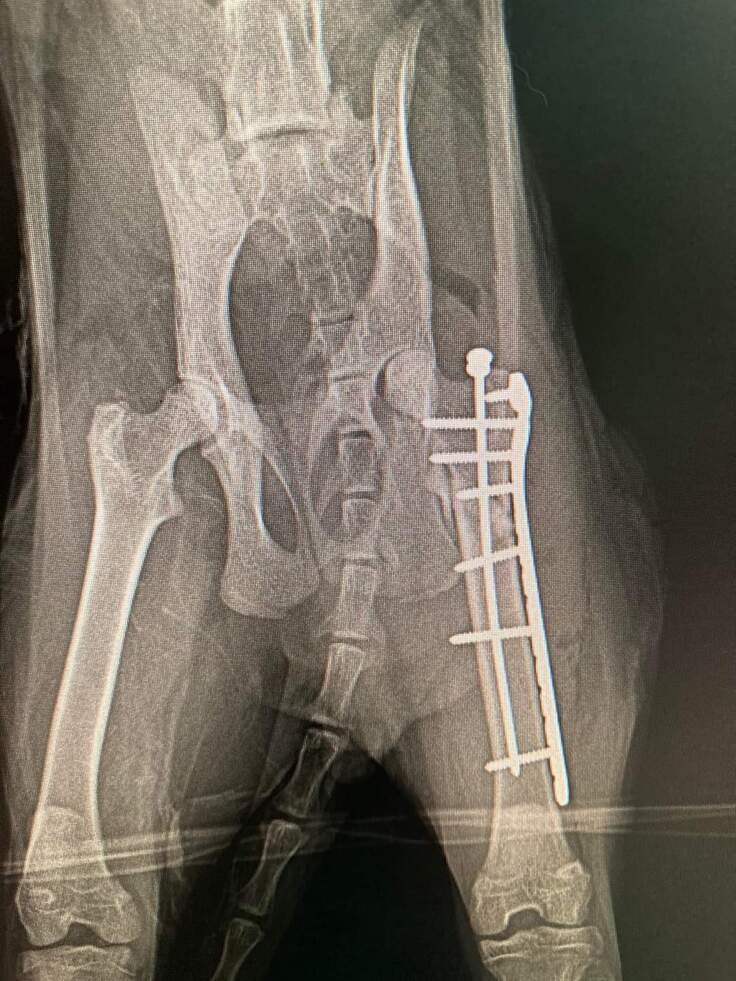

今回は、交通事故に遭ったモリくんをご紹介します。

事故に遭ったモリくんと名付けられた猫は、顎と骨盤、脚の複雑骨折の手術が必要な状態でした。

術後も自分でご飯を食べて、排泄ができるようになるのか。経過が心配されましたが、断脚することなく回復してくれました。